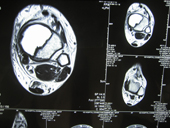

| Giant cell tumour MRI |

MRI2 |

MRI3 |

Joseph Hospital's Tumor & Bone disease service benefits from the experience and expertise of experts.The team treats bone tumors and soft tissue tumors in collobaration with Radiotherapists and Surgical Oncologists . Limb salvage is done with radical excision of the tumour and reconstruction with prosthesis in lieu of amputations.